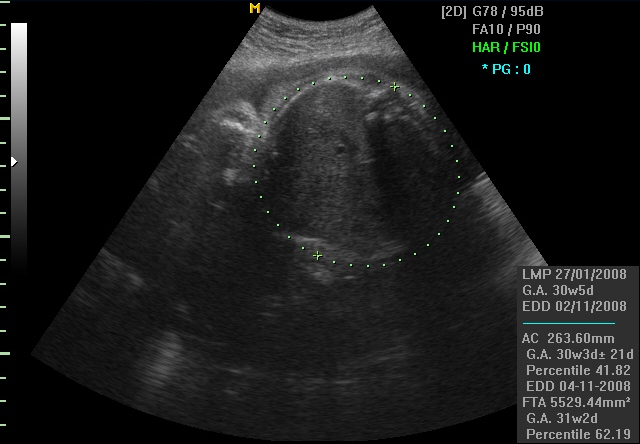

AC (Abdominal circumference) е мерка на обемот на стомачето на бебето. Таа се користи за мерење на растот на бебето, за одредување на тежината и големината на плодот.

Од сите овие мерки може да се пресмета приближната тежина на плодот во дадениот момент.